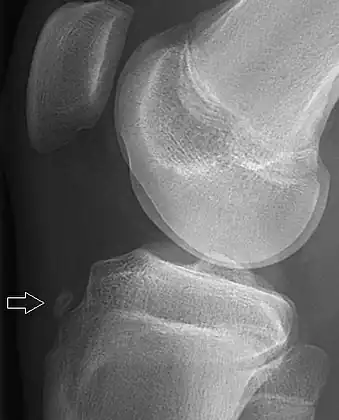

Tuberosity avulsion of the 5th metatarsal

Proximal fractures of 5th metatarsa

The tuberosity avulsion fracture (also known as pseudo-Jones fracture or dancer's fracture[2] is a common fracture of the fifth metatarsal (the bone on the outside edge of the foot extending to the little toe).[3] This fracture is likely caused by the lateral band of the plantar aponeurosis (tendon).[4]

Most of these fractures are treated with a hard-soled shoe or walking cast. This is needed until the pain goes away and then the patient can return to normal activities.[3] Healing is usually completed within eight weeks.[5]